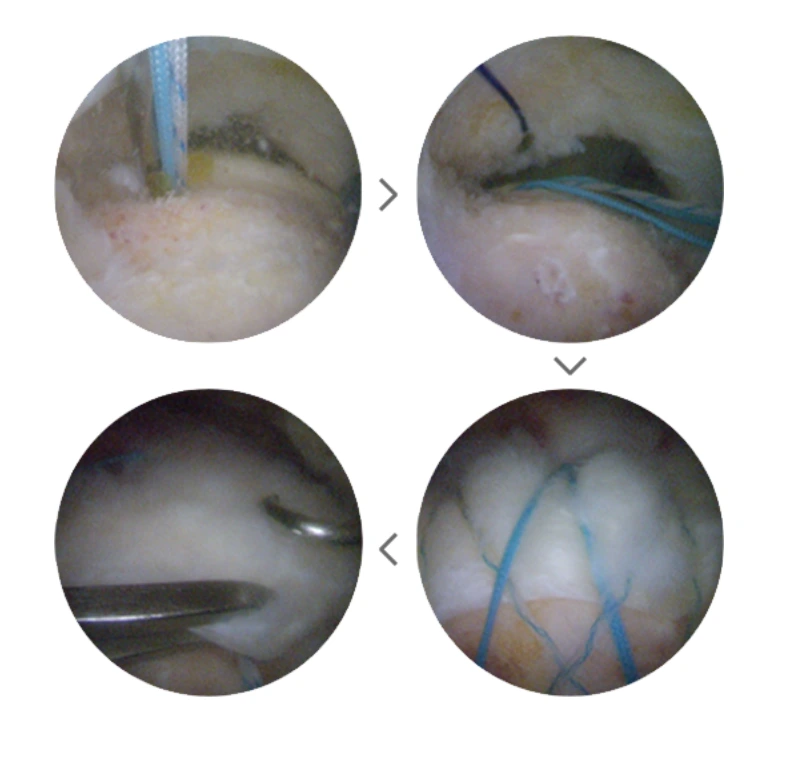

타가 힘줄 이식술

광범위하게 회전근개가 파열되면 간단한 봉합만으로는 제 기능을 하지 못하게 되지요. 이런 경우에는 바깥층 부분의 힘줄이 지방조직으로 변해 소실이 되는 경우가 많기 때문에 봉합하더라도 결손 부위가 남게 되어 완전봉합이 불가능하기 때문입니다.

따라서 사람의 피부 구조와 동일한 동종진피를 이용해 힘줄을 이식하는 타가 힘줄 이식술을 진행하는데요. 힘줄이 변성되고 소실되어서 동종진피를 덧대는 1차 봉합 후 브릿지 이중 봉합을 시행합니다.

타가힘줄이식술.PNG